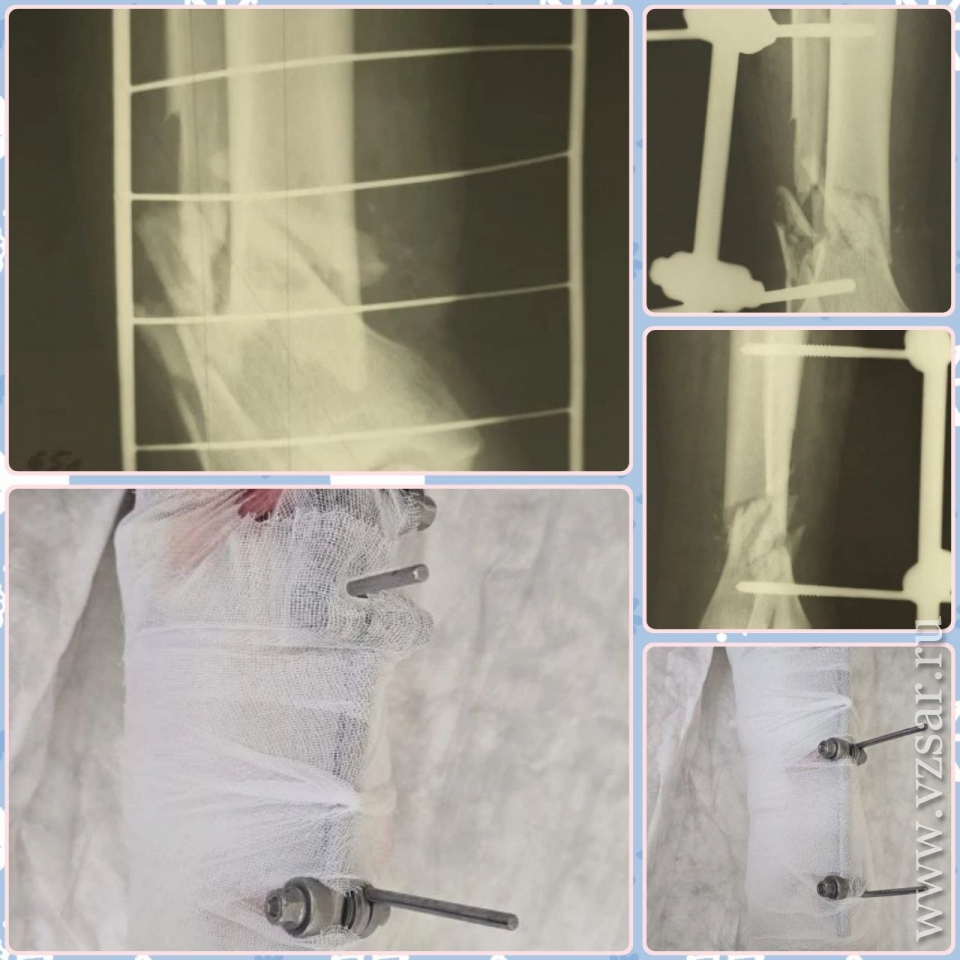

Другой случай: 65-летний мужчина упал со стремянки во время мытья окон. Результат – тяжелый открытый многооскольчатый перелом обеих костей голени со смещением. Врачи стабилизировали кости аппаратом внешней фиксации, но пациента ждет реабилитация до 8 месяцев.